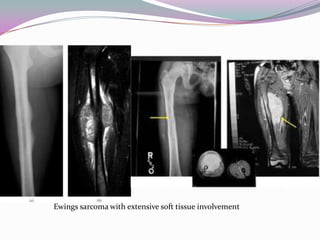

Ewings sarcoma with extensive soft tissue involvement

Ewings sarcoma withextensive soft tissue involvement